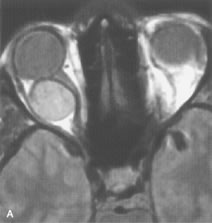

PATIENT PREPARATION Before MRI is performed, patients must be screened and prepared to avoid the potential hazards associated with the strong magnetic field. Patients who have ferrous aneurysm clips or cardiac pacemakers, who depend on life-support equipment, or who retain a possible metallic intraocular foreign body are not candidates for this imaging modality. MRI cannot be performed on obese patients who cannot fit into the bore of the magnet. Patients who are claustrophobic may not tolerate a prolonged period of study within the confines of the magnet, whereas others might do well if given a mild sedative. All worn metallic objects (e.g., necklaces, watches) should be taken off, credit cards set aside, and eye makeup removed before entering the room containing the magnet.5,20,34,35,36 NORMAL ORBITAL ANATOMY T1-weighted images provide the best anatomic details of the orbit because they display superior contrast resolution between normal structures (see Fig. 8). The vitreous has a long T1, resulting in an intermediate signal similar to brain, whereas the crystalline lens and sclera appear dark because of a longer T1 and short T2. The extraocular muscles, like all skeletal muscles, demonstrate a moderately long T1 and short T2 and highly contrast with the intense signal of the surrounding orbital fat (adipose tissue has an extremely short T1). The lacrimal glands appear as mottled areas of reduced intensity of the signal from the orbital fat in the lacrimal fossa. The optic nerves are seen with the same signal intensity as brain white matter and are hypointense relative to the orbital fat because their Tl is longer than the Tl of fat but shorter than the Tl of water. Cortical bone is not well delineated because it contains little free water, yielding minimal signal in MRI, and thus appears dark on all pulse sequences. This feature explains why MR images of the orbital apex and intracanalicular portion of the optic nerves are superior to comparable CT scans. Partial volume averaging of the bones in these regions obscures soft tissue details on CT images, whereas MRI reveals the signals only from the soft tissue structures with no cortical bone input. Bone marrow, on the other hand, is seen as a relatively intense signal because of its high fat content (see Fig. 8).37,38 T2-weighted pulse sequences are not ideal for imaging normal anatomy; however, they are particularly useful in revealing pathologic conditions (see Fig. 9). T2-weighted studies are most easily recognized by a bright vitreous signal. ORBITAL DISEASES Vascular Lesions Cavernous hemangiomas appear as well-circumscribed, smooth, usually intraconal masses that are isointense to muscle on T1-weighted images and hyperintense on T2-weighted images (Fig. 12). Patchy early enhancement is typically followed by diffuse, more homogeneous enhancement.39 The internal architecture of the mass, including septation and internal vasculature, may often be appreciated with high-quality orbital imaging.40 Lymphangiomas consist of ectatic vascular channels within a connective tissue stoma with varying degrees of lymphoid cellularity. On MRI, these tumors are typically poorly circumscribed, multicompartmental, and heterogeneous, often showing cystic dilations with fluid levels (Fig. 13). The signal characteristics within lymphangiomas vary considerably, reflecting cystic and solid components and the varying paramagnetic characteristics of blood at different stages of degradation.40–42 Acute hemorrhage appears hypointense on both T1- and T2-weighted formats. Methemoglobin present in subacute hemorrhage (3 to 14 days) leads to hyperintense signal on both T1- and T2-weighted images.41 A small percentage of lymphangiomas appear radiologically indistinct from orbital cavernous hemangiomas.43 Orbital varices are venous malformations that expand with increased systemic venous pressure, such as with Valsalva maneuvers. Because rapid acquisition of images during a Valsalva maneuver is important in imaging such a lesion, conventional or spiral CT is currently the modality of choice.44 MRI is an excellent modality for demonstrating enlargement of the cavernous sinus and dilation of the superior ophthalmic vein in patients with high-flow carotid-cavernous fistulas (Fig. 14).37MRA may be helpful in the evaluation of the venous outflow pattern. The rapidly flowing blood in these vascular structures carries the excited protons out of the section before they can be imaged, resulting in their dark appearance.5 In low-flow dural arteriovenous malformations, MRA may help define the arterial feeding vessels.45 Neural Lesions MRI is more effective than CT in delineating the intracranial optic nerves, chiasm, and optic tracts and, for this reason, is the preferred imaging modality in the evaluation of optic nerve disorders. The spatial relationships and image contrast of the orbital tissues with intraorbital optic nerve tumors is comparable between the two imaging modalities. The normal nerve is isointense to brain and appears enlarged and kinked owing to infiltration of an optic nerve glioma on T1-weighted images. Gliomas appear hyperintense on T2-weighted images and may be heterogeneous owing to cystic areas within the tumor. Contrast enhancement is variable.46 Intraorbital and intracranial optic nerve sheath meningiomas are usually isointense to cortical gray matter on Tl-weighted images and remain isointense on proton density studies (Fig. 15). Gd-DTPA is useful in delineating the intracranial extension of optic nerve meningiomas.7,47 The hyperostosis of bone and calcification associated with meningiomas are not demonstrated as well on MRI studies as on CT scans.20,37 Gd-DTPA–enhanced MRI also appears promising in the study of the permeability of the blood–brain barrier in selected optic neuropathies.22,48 MRI may reveal an enlarged optic nerve and some degree of contrast enhancement in cases of optic neuritis.49 Muscle Disorders Extraocular muscle enlargement in patients with thyroid-associated orbitopathy is demonstrated equally well with CT and MRI studies. However, the superior tissue contrast on MR images reveals better details of the relationships of the optic nerve to the thickened muscles at the orbital apex (Fig. 16).50 In addition, MRI may be able to differentiate between muscles that are enlarged as a result of edema and active inflammation and those enlarged because of fibrosis by their T2 relaxation times.21 Quantitative MRI was not found to be accurate in predicting the success of low-dose orbital irradiation.51 However, a muscular index relating the diameters of the rectus muscles to the bony orbital dimensions was useful in predicting optic nerve compression.52 MRI is also effective in imaging orbital tumors of mesenchymal origin, such as rhabdomyosarcoma, particularly in the assessment of extension into the anterior and middle cranial fossae (Fig. 17).37 The lack of any pathognomonic radiologic features necessitates rapid orbital biopsy when rhabdomyosarcoma is suspected. Osseous Lesions In general, CT is the imaging modality of choice when details of quantity and quality of bone are needed; however, abnormalities of bones can be detected indirectly by MRI. Cortical bone appears black (signal void) on MR images because of its low proton density and free-water content. The absence or discontinuity of the signal void of the orbital walls may represent bony destruction or fracture. Hyperostosis associated with prostate metastases or meningioma is visualized as areas of black smudging.50,53 Diseases in which the bone is replaced by pathologic tissues with a high free-water content, such as fibrous dysplasia, are well demonstrated on MRI. An intermediate signal intensity on T1-weighted images and hypointense signal on T2-weighted images is representative of fibrous dysplasia. Enhancement on post–Gd-DTPA MR scans is seen and is more evident in areas that are less mineralized.54 Cystic Lesions Dermoid cysts appear as rounded, well-defined lesions typically contiguous with an orbital bony suture. The high-intensity signal on T1-weighted images is attributed to the sebaceous-produced lipid contents (Fig. 18).31,50 Mucoceles may demonstrate a hypointense or hyperintense signal on MR images, depending on the concentration of proteinaceous or inflammatory fluid components. The integrity of the bony walls of the expanded sinus cavities cannot be assessed on MR as well as by CT.37,50,55,56 A high-signal intensity on Tl- and T2-weighted images is characteristic of orbital chronic hematic cysts because of the blood-breakdown products within the cysts.57 Trauma Although soft tissue relationships are usually better demonstrated on MRI, the evaluation of craniofacial bony trauma is preferable with CT. For example, prolapse of orbital fat through a fracture site and hemorrhage of adjacent tissues are demonstrated in an MR image, but the actual fractured bone is not imaged. Three-dimensional MRI of the orbit in subacute trauma has been described,58 although its precise role is not currently established. MRI has been suggested to be superior to CT in detecting intraorbital wooden foreign bodies.59,60 In a series of penetrating orbital injuries with organic foreign bodies, however, MRI was able to identify the foreign body in only four of seven cases.61 With an in vitro model for wood foreign body, McGuckin and colleagues concluded that CT was the imaging modality of choice.62 A careful history and, in selected cases, plain films to rule out a metallic foreign body are crucial before MRI is considered in patients with periocular trauma. MRI is particularly helpful in the detection and characterization of subperiosteal hematomas of the orbit (Fig. 19). They are most commonly seen in the subperiosteal space of the superior orbit as well-defined masses following a traumatic injury. The signal intensity varies depending on the acute, subacute, or chronic nature of the hematoma, based on the stage of blood degradation. Fresh hemorrhages are hypointense on T1-weighted images and hyperintense on T2 images. Hematomas that are 1 to 7 days old are hypointense on both T1- and T2-weighted images. T1-weighted images of hematomas more than a week old are hyperintense due to the oxidation of deoxyhemoglobin to methemoglobin, whereas the T2 images remain hypointense.63 Metastatic Tumors Breast carcinoma metastatic to the orbit has been demonstrated to be hypointense to the surrounding orbital fat on T1-weighted studies and hyperintense on T2-weighted images and has an affinity to the extraocular muscles (Fig. 20).50,64 The MRI characteristics of prostate carcinoma metastatic to the orbit have been described as involving the greater and lesser wing of the sphenoid, orbital roof, and optic canal. Diffuse bone hypertrophy with isointense or slightly hyperintense tissue on T1-weighted images represents the osteoblastic carcinomatous bone infiltration. Contrast enhancement is variable on T1-weighted and fat-suppressed images.65 Most other metastatic tumors also have a lower intensity signal on T1-weighted images and appear to displace or infiltrate normal orbital structures; however, their signal characteristics are variable on T2-weighted MR images.66 Many metastatic tumors demonstrate bright contrast enhancement with Gd-DTPA. Infectious Disorders MRI findings of preseptal and orbital cellulitis typically include increased signal intensities on T2-weighted images of the eyelids and orbital fat, respectively, due to the increased water content of the tissues. Since most cases of bacterial orbital cellulitis are associated with paranasal sinusitis, hyperintense signals of the affected sinuses may also be found on T2-weighted images as well as enhancement of polyps and granulation tissue on postgadolinium T1-weighted MR images. Subperiosteal abscess formation may occur due to contiguous spread of infection from the paranasal sinuses and appear on MRI as an area of intermediate signal on T1-weighted and proton-weighted MR images. The abscess may appear slightly hyperintense compared with muscle on T2-weighted scans with the necrotic contents having the greatest intensity.67 MRI and MRV are more sensitive than CT in revealing cavernous sinus thrombosis. Engorgement of the cavernous sinus, extraocular muscles, and ophthalmic veins is seen with hyperintensity of the thrombosed sinuses evident on all pulse sequences. The enlarged, thrombosed superior ophthalmic vein appears less hypointense than the normal contralateral ophthalmic vein, and hyperintensity within the lumen of the vessel may be seen on T1- and T2-weighted MR images.68 Inflammatory and Lymphoproliferative Lesions Inflammatory conditions of the orbit, both idiopathic (inflammatory pseudotumor) and those of known causes, have been found to be hypointense to fat and isointense to muscle on Tl-weighted studies and isointense or slightly hyperintense to fat on T2-weighted images (Fig. 21).50,64,69 The more fibrous or sclerosing varieties have less signal intensity on T2-weighted images. Marked enhancement is seen in pseudotumor infiltrates after gadolinium administration.70 The same signal characteristics are demonstrated in patients with Tolosa-Hunt syndrome, with mass lesions seen in the cavernous sinuses and orbital apices.71 Lymphomas have MRI characteristics similar to those of inflammatory lesions in that they are hypointense to fat and isointense to muscle on T1-weighted images (Fig. 22). They may appear hyperintense to fat on T2-weighted images, perhaps owing to less fibrosis than that seen in orbital inflammatory pseudotumor, although this is not a consistent finding.31,50,66 Lymphoid tumors typically enhance moderately after contrast injection. Unfortunately, studies have shown that tumor density and homogeneity are similar between inflammatory and malignant orbital infiltrates, and MRI cannot differentiate these lesions.72,73 Lacrimal Gland Tumors Lacrimal gland lesions present special problems in diagnosis and management. Pleomorphic adenoma (benign mixed tumor) should not be biopsied, but rather excised in toto. On the other hand, for lymphoma and inflammatory infiltrates, incisional biopsy is more appropriate than complete excision of the lacrimal gland. Thus, preoperative clinical and radiologic evaluation are especially crucial in planning appropriate surgical management. Pleomorphic adenomas demonstrate long T1 and T2 signal characteristics. They may show heterogeneity on T2-weighted images74 and moderate to marked enhancement with contrast.75 Signal characteristics of adenoid cystic carcinoma include hypointensity to fat on T1-weighted images, hyperintensity to fat with increased T2 weighting, and isointensity to fat on proton density-weighted studies (Fig. 23).31,75 Secondary bony alterations of the lacrimal fossa associated with lacrimal gland tumors, such as remodeling (benign mixed tumor) or destruction (adenoid cystic carcinoma), are seen indirectly on MR images; however, bone windows on CT scans provide better delineation of these changes. In contrast to the round or globular appearance of benign or malignant epithelial tumors of the lacrimal gland, lymphoproliferative tumors usually appear to be molding or draping onto the globe and the surrounding bony orbit. LACRIMAL DRAINAGE SYSTEM DISORDERS MRI with surface coils provides excellent spatial resolution and tissue-specific signal intensities of the lacrimal drainage system. These parameters have been found useful to more accurately demonstrate the extent of lesions in the lacrimal sac and differentiate long-standing mucoceles from solid tumors than CT.76 Physiologic studies in patients with tearing disorders now include MR dacryocystography, in which Gd-DTPA is either placed topically in the conjunctival fornix or injected by cannulation into the lacrimal sac. They provide a detailed morphologic and functional analysis of the lacrimal excretory system; however, they are no more sensitive than digital-subtraction dacryocystography or CT dacryocystography.77–79 INTRAOCULAR TUMORS On MRI, uveal melanomas have a typical appearance that helps to differentiate them from other primary and secondary intraocular tumors as well as choroidal detachments. Pigmented melanomas are hyperintense on Tl-weighted images, hypointense on T2-weighted studies, and hyperintense on proton density–weighted examinations (Fig. 24).30,31,50,80–82 These signal characteristics have been attributed to the paramagnetic properties of melanin because of stable free radicals that shorten the T1 and T2 relaxation times. Moderate enhancement is seen on postgadolinium T2-weighted images. Gadolinium-enhanced T1-weighted images are particularly sensitive in detecting choroidal melanomas.83 MRI may be less sensitive in detecting extrascleral extension of tumor than echography performed by an experienced ultrasonographer.84 Tumors metastatic to the choroid are hyperintense on T1- and T2-weighted images.24 The signal characteristics, however, may be similar to those seen with choroidal melanoma. Choroidal hemangiomas, on the other hand, have an intermediate signal on T1-weighted sequences and become hyperintense on T2-weighted images50 as well as proton density–weighted images.81 Retinoblastomas display moderate signal intensity on T1-weighted studies and a low signal on T2-weighted images.31,80,85 Calcification can be easily detected by CT and ocular ultrasonography but is not imaged by MRI.25,50 The presence of optic nerve involvement is best evaluated by MRI. ACQUIRED ANOPHTHALMIA When an eye is removed owing to tumor or trauma, an implant is typically placed in the intraconal space. MRI may be useful in defining the size, shape, and position of such orbital implants.86 Porous hydroxyapatite or polyethylene implants are preferred by many surgeons performing enucleation or evisceration. A porous implant offers the possibility of supporting a motility coupling peg to increase the movement of the overlying prosthesis. MRI with contrast is used by some surgeons to evaluate the degree of fibrovascular ingrowth in hydroxyapatite87 and porous polyethylene88 implants prior to motility peg placement. |